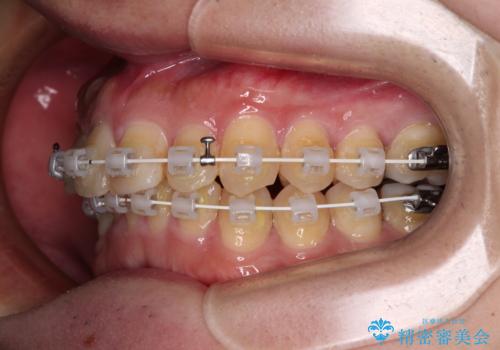

- 矯正装置

- 審美装置

- 1年4ヶ月

- 10-30回

- 深い咬み合わせによる食いしばりで、顎関節や頭が痛むことがあるとのことで来院された患者様です。

歯ぎしりができないくらい強い食いしばりの咬合状態であったため、奥歯の歯軸を起き上がらせることで咬合を挙上させ、歯ぎしりができるようにしていくこととしました。

インビザラインでの矯正治療も可能でしたが、自己管理の煩わしさを嫌ってワイヤー装置による矯正治療を行うこととしました。